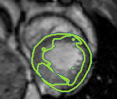

4.2 Visual assessment

We select the case that achieves the highest and lowest dice score for visual assessment. Fig. 4 shows example segmentation results where the proposed method achieved the highest agreement with the ground truth delineations. Fig. 5 shows example segmentation results where the proposed method achieved the lowest agreement with the ground truth delineations.